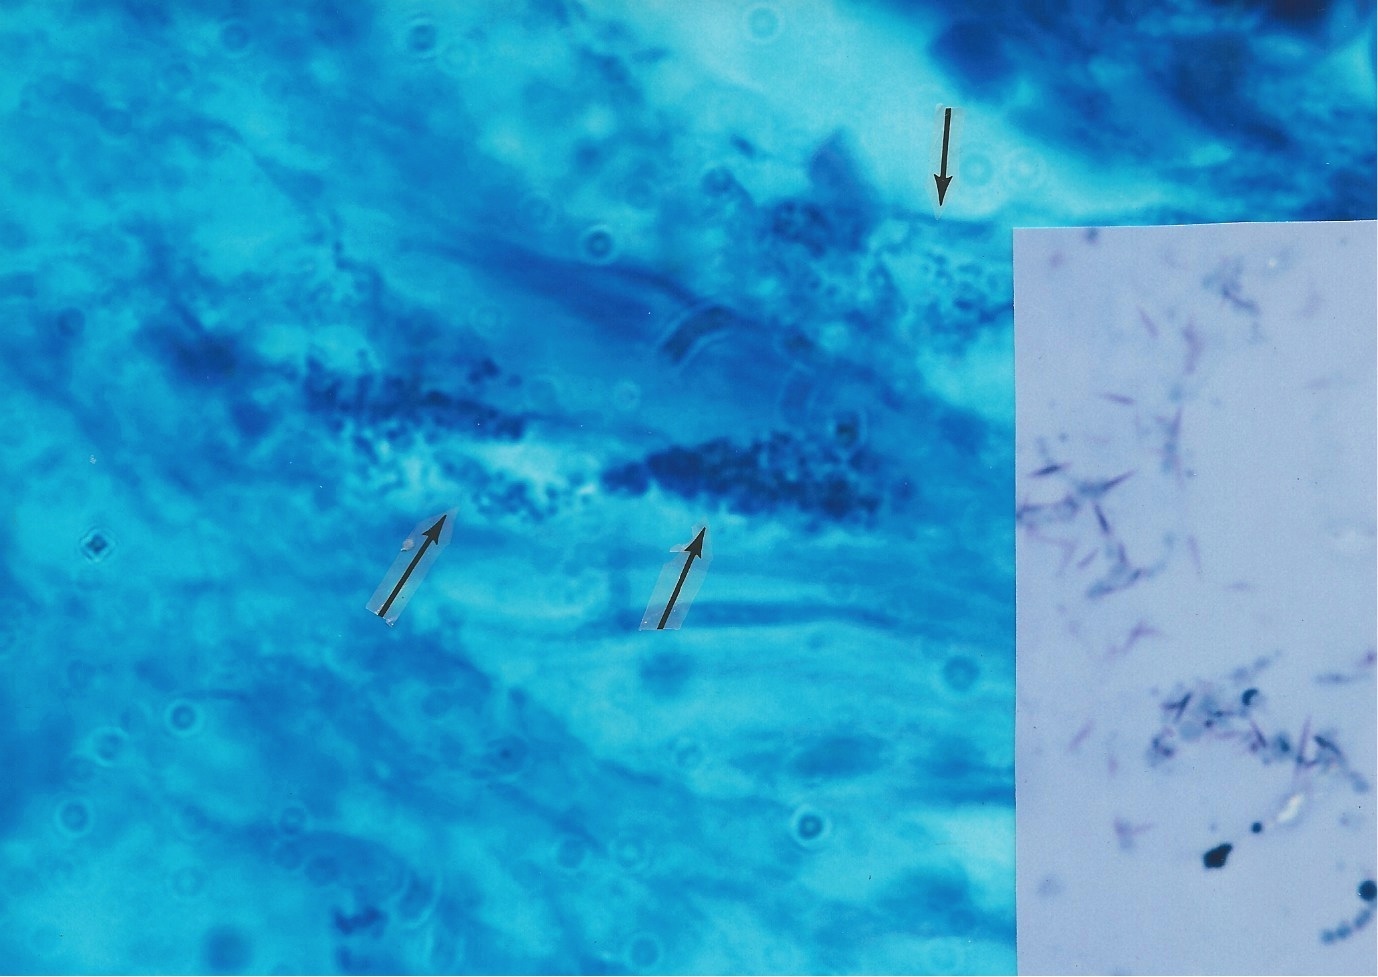

Figure 6. Bone marrow section taken from autopsy of a fatal case of AIDS. A Giant Large Body appears to

be budding, similar to what some fungi do. Fite (acid-fast) stain, x10

Figure 7. Unstained transparent, large balloon-like forms and related small coccoid growth forms of

Mycobacterium tuberculosis

observed and photographed by use of the phase contrast microscope.

(from, Conrado Xalabarder, L-forms of Mycobacteria and Chronic Nephritis, 1970, p 51

Figure 10. AIDS-related Kaposi’s sarcoma of the skin. Arrows point to intra-and extracellular coccoid forms in the dermis. Fite (acid-fast) stain, x1000.

Inset shows appearance of cocco-bacillary corynebacteria cultured from the tumor. Ziehl-Neelsen (acid-fast) stain, x1000.

Figure 11. Skin tumor of AIDS-related immunoblastic sarcoma showing three very rare acid-fast rod forms of mycobacteria in the dermis.

Fite (acid-fast) stain, x1000. Mycobacterium avium-intracellulare was cultured from the tumo

If one carefully observes smears made from culture of the non-tuberculous Mycobacterium avium-intracellulare, it is evident that this microbe is pleomorphic. Easily overlooked are the non-acid-fast, blue-stained coccoid forms and the still smaller, barely visible light blue granular forms seen in Figure 12. If a culture of CWD mycobacteria consists predominantly of CWD coccal forms, it could easily be misinterpreted as common staphylococci or other micrococci and dismissed as a “contaminant.” For that reason, all smears showing coccal and cocco-bacillary forms cultured from cancer should be subjected to an acid-fast stain. Livingston always stressed the cancer microbe could be identified by its intermittent acid ­fastness. Occasionally, smears reveal acid-fast “spicules” emanating from the cocci, as noted in the streptococci cultured from KS (see, the inset of Figure 8). The exact significance is not clear, but the spicule phenomenon was reported by Livingston and Alexander-Jackson in some of their cancer isolates, and may serve as an additional clue to a possible mycobacterial origin of the lab culture [50].

Figure 12. Smear of pleomorphic Mycobacterium avium-intracellulare cultured from immunoblastic sarcoma

Arrows point to a small area of non-acid-fast (blue-stained) staphylococcal-sized cocci and to smaller pale blue-staining granular forms.